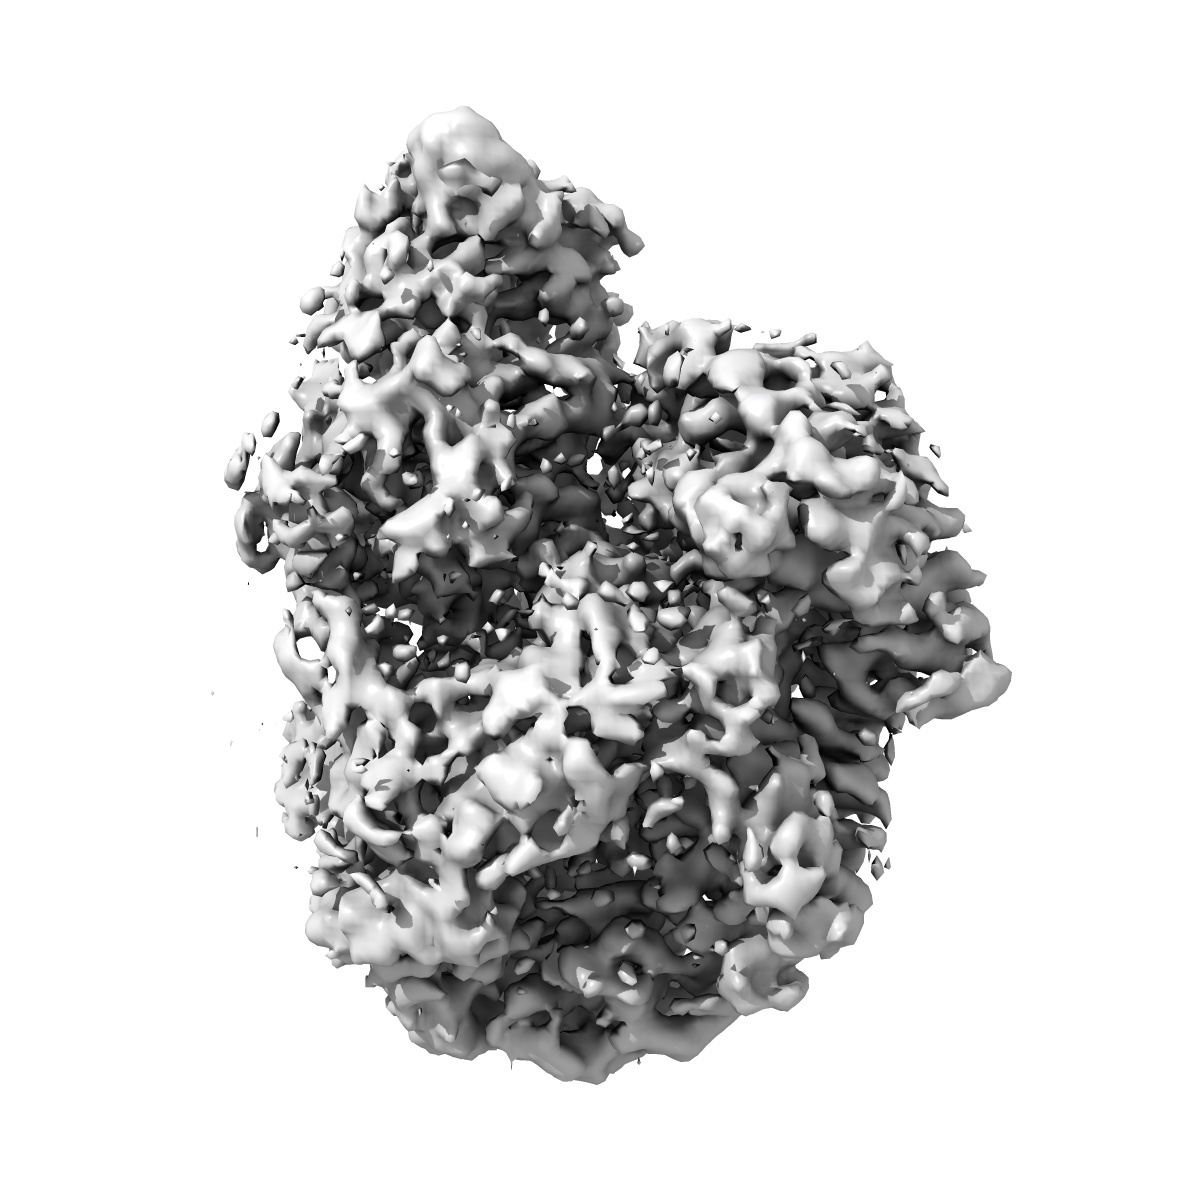

Cryo-EM Structure of the BRAF V600E monomer bound to PLX8394

Single-particle3.06 Å

Sample: BRAF V600E - 14.3.3 complex bound to PLX8394

BRAF oncogenic mutants evade autoinhibition through a common mechanism.

(2025) Science , 388 , eadp2742 - eadp2742